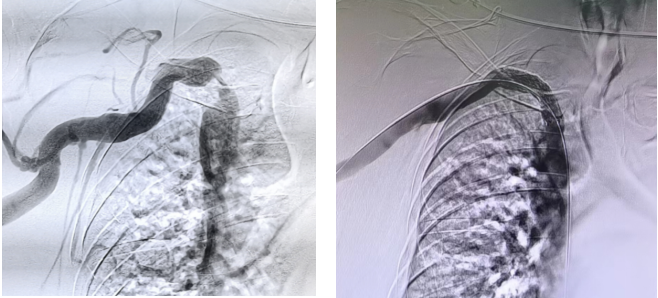

首例入组患者为动静脉内瘘透析患者,透析6年,右上肢肿胀多日入院。经血管内造影查看,患者右侧无名静脉重度狭窄。随机至试验组后,经研究团队精心评估准备,由崔天蕾教授团队顺利完成无名静脉植入药物涂层血管覆膜支架手术,解除了重度狭窄病变,右上肢静脉血液回流恢复通畅,患者肢体肿胀感消失,临床治疗效果显著。研究者对覆膜支架的使用和临床表现给予充分肯定。

患者术前、术后影像对比